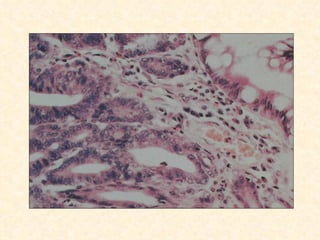

Esôfago de Barret

Refluxo GE recorrente e prolongado

Inflamação

Ulceração

Cura por reepitelização e crescimento

de células pluripotentes imaturas

ph no lúmem do esôfago distal causa diferenciação

Da mucosa para epitélio intestinal

Esôfago de Barret Refluxo GE recorrente e prolongado Inflamação Ulceração Cura por reepitelização e crescimento de células pluripotentes imaturas ph no lúmem do esôfago distal causa diferenciação Da mucosa para epitélio intestinal